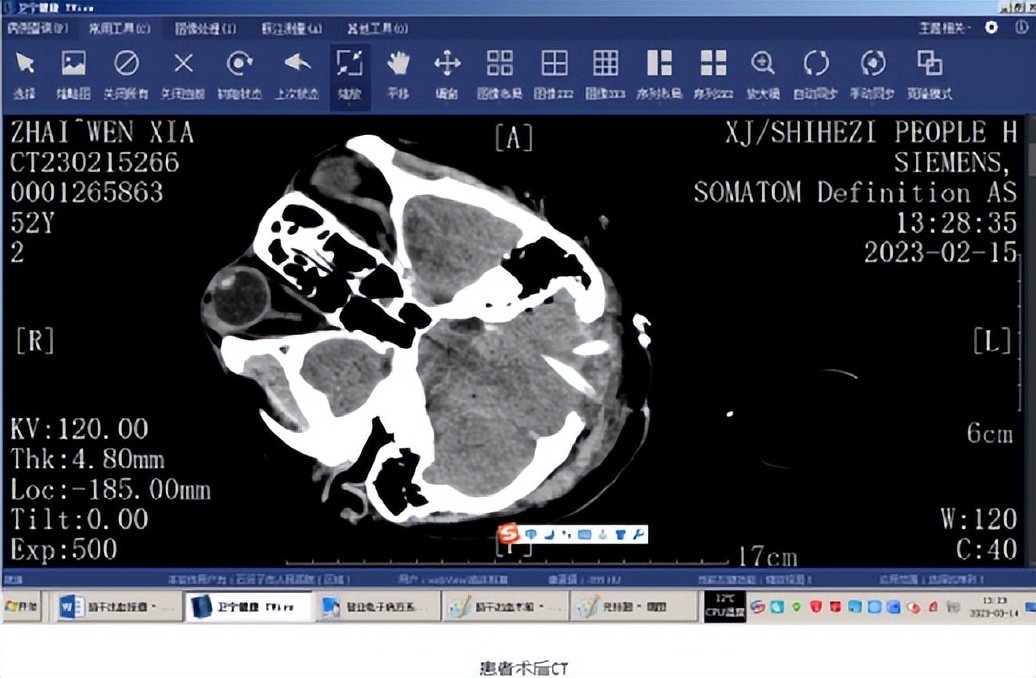

2023年2月13日,1名52岁女性患者以“发现呼吸不应3小时余”为主诉到石河子市人民医院就诊。医生立即查体GCS评分6分,深度昏迷,双侧瞳孔扩大约4mm,对光反射消失,四肢肢体肌力0级。头部CT显示脑干左部-左侧桥臂脑出血,出血量约5ml。该患者2020年曾丘脑出血保守治疗并恢复良好。

入院后,神经外科医疗团队经过仔细的病例讨论,综合各种手术方式的利弊,决定为患者施行经小脑脑桥角入路脑干血肿清除术,术后患者清醒,有部分吞咽反射、咳嗽反射功能障碍及心动过速,经过该科及重症医学科医护人员的精心治疗,患者以上症状很快恢复,共住院27天,患者可以下地行走,四肢肌力正常,各种反射恢复良好。